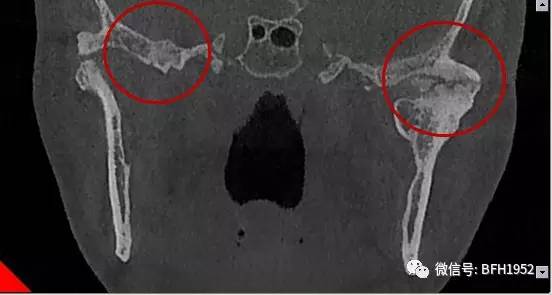

患者为一名57岁女性,3年前因从高处坠落受伤导致颞下颌关节强直,引起张口受限和咬合关系紊乱,严重影响进食。入院检查后发现患者张口度仅为8mm,锥形束CT(CBCT)检查可见左侧髁突原骨折部位形成骨球与颅底融合;磁共振成像(MRI)可见髁突内侧存在髁突小头,表面覆盖关节盘。

术前